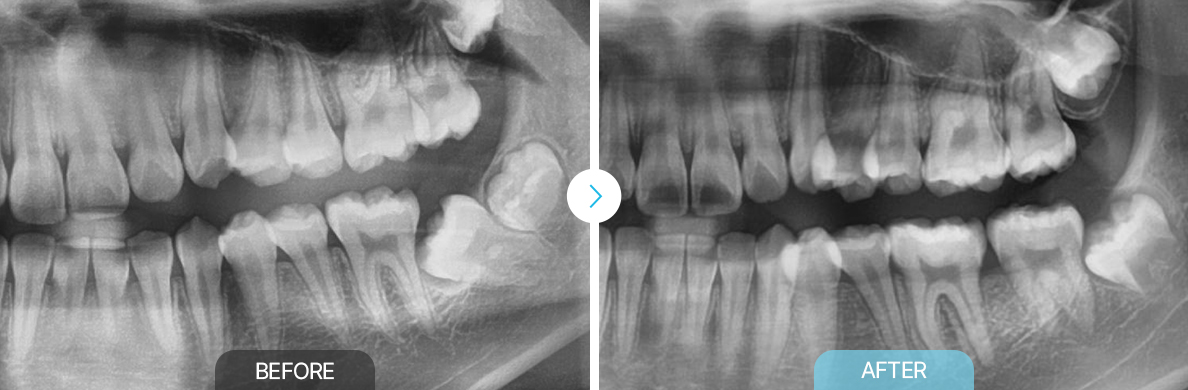

BEFOREAFTER

앞니급속교정